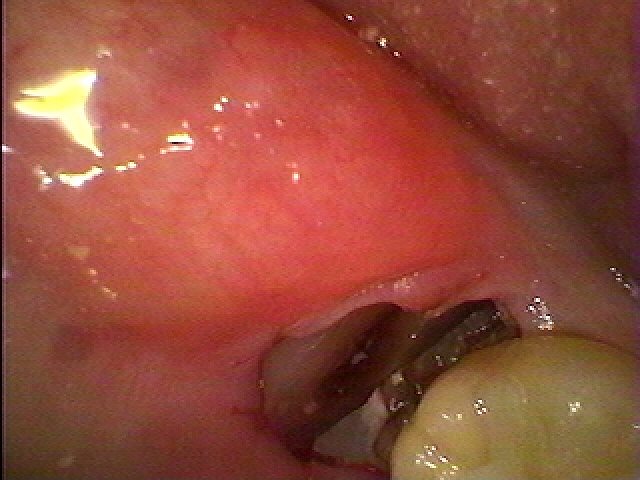

ここに親知らずが埋まっています

分割抜歯を行っています

歯間部を分割していきました

切開することなく抜歯を行いました